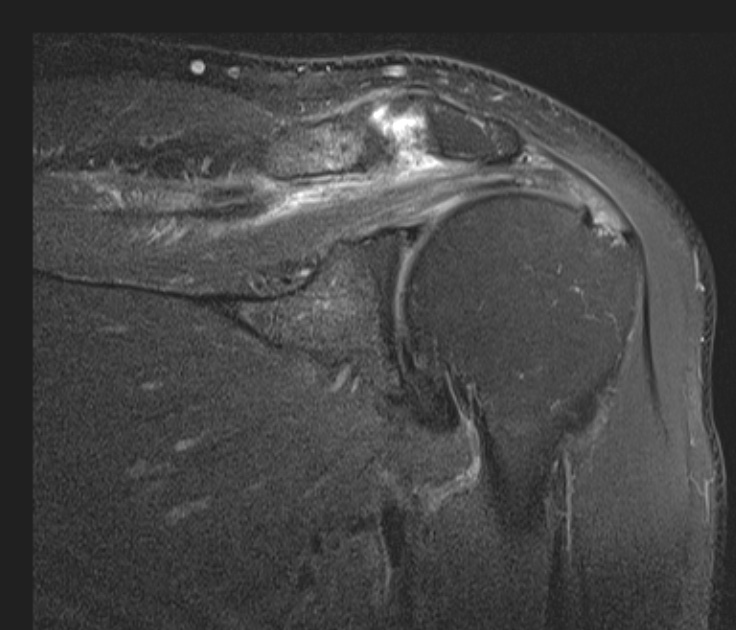

The surgeon said the tear wasnt visible from the articular side and debridement was necessary to reach it from the bursa. The tendon was stuck down and a side to side repair was necessary. You can make out the central defect in the footprint with intact articular and burial surfaces.

I have seen a few of these in Infraspinatus, as per the article linked below, but this was my first in Supraspinatus. Reference article.

Massive interstitial delamination of Supraspinatus with retraction